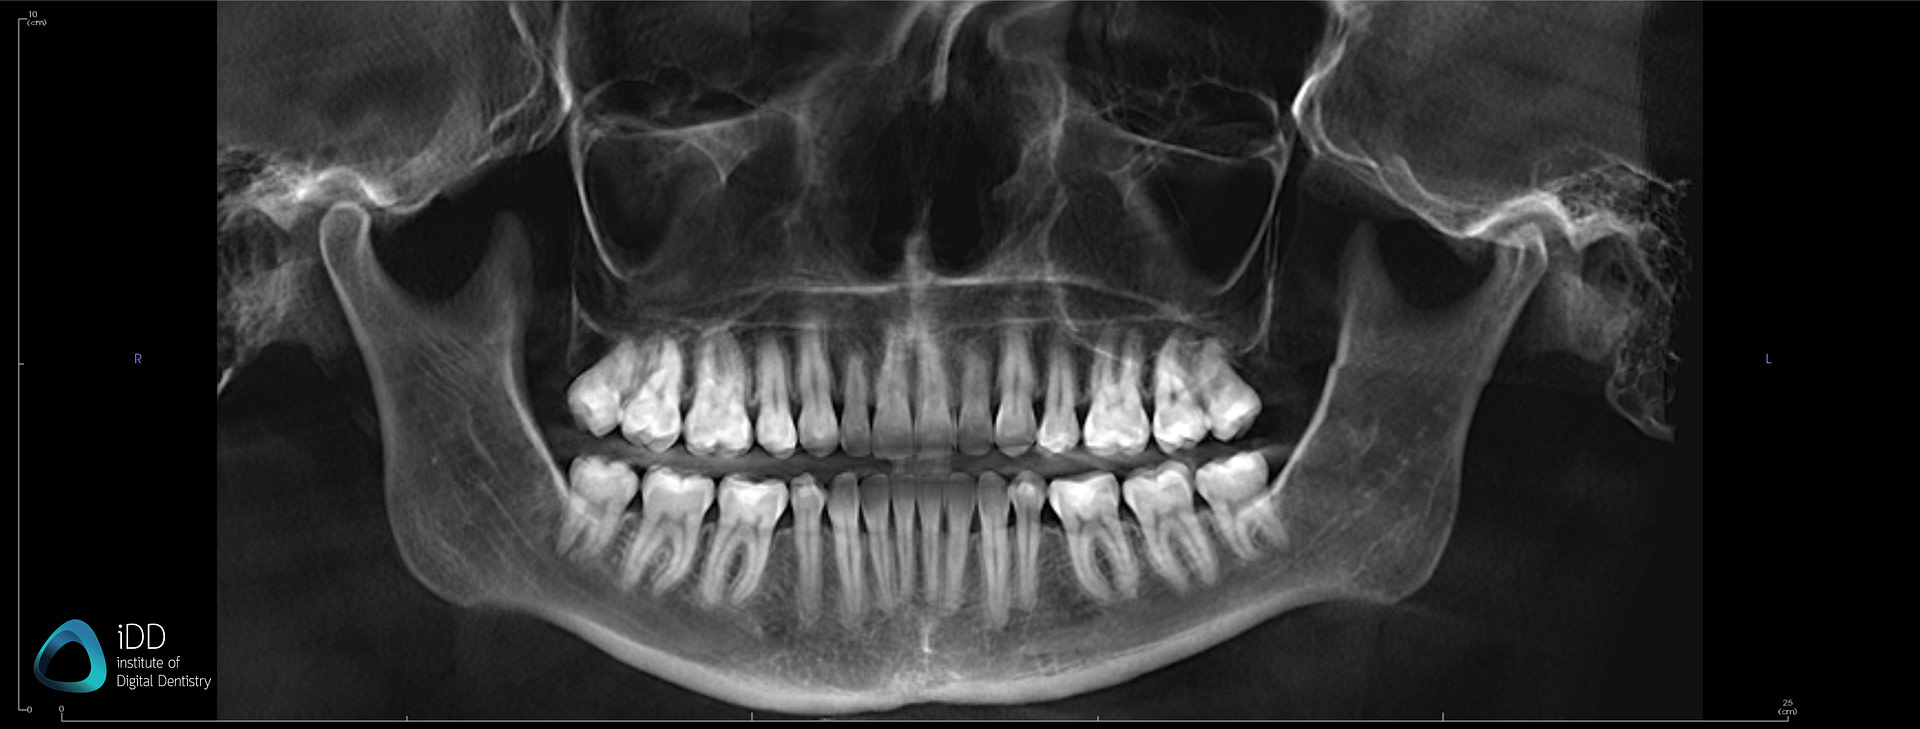

Modern dental CBCT systems are defined by three interdependent subsystems: X-ray generation, photon detection, and computational reconstruction. 2026 advancements target quantum efficiency, spatial resolution, and algorithmic fidelity.

Key Innovation: Tungsten-rhenium alloy anodes with liquid metal cooling enable sustained 120kVp operation at 15mA without thermal throttling. Dynamic collimation adjusts beam geometry in 50μs increments based on patient attenuation maps from pilot pulses.

Clinical Impact: Reduces dose variance by 32% (IEC 61223-3-5 compliant measurements) in heterogeneous anatomy (e.g., zygomatic regions), eliminating overexposure in mandibular scans.

- Metal Artifact Reduction: Dual-energy PCD data feeds a U-Net architecture trained on synthetic metal artifacts. Solves linear attenuation coefficient (μ) inconsistencies via constrained optimization (L1-norm regularization). Reduces streak artifacts by 68% (measured via RMSE in titanium regions).

Clinical Impact: Enables sub-millimeter implant planning accuracy (0.12mm RMS error in 3D landmark studies) even with full-arch zirconia bridges present.

Each sensor undergoes pre- and post-assembly calibration under controlled temperature (±0.5°C) and humidity (45–55% RH) conditions, ensuring spatial resolution consistency down to 75 μm voxel resolution across clinical field-of-view (FOV) settings.